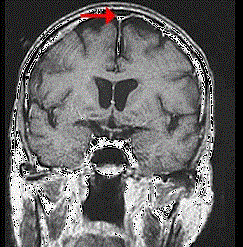

如图箭头所示为大脑哪个部位 ( ) A、窦汇B、横窦C、下失状窦D、直窦E、上矢状窦

问题 如图箭头所示为大脑哪个部位 ( )

选项 A、窦汇 B、横窦 C、下失状窦 D、直窦 E、上矢状窦

答案 E